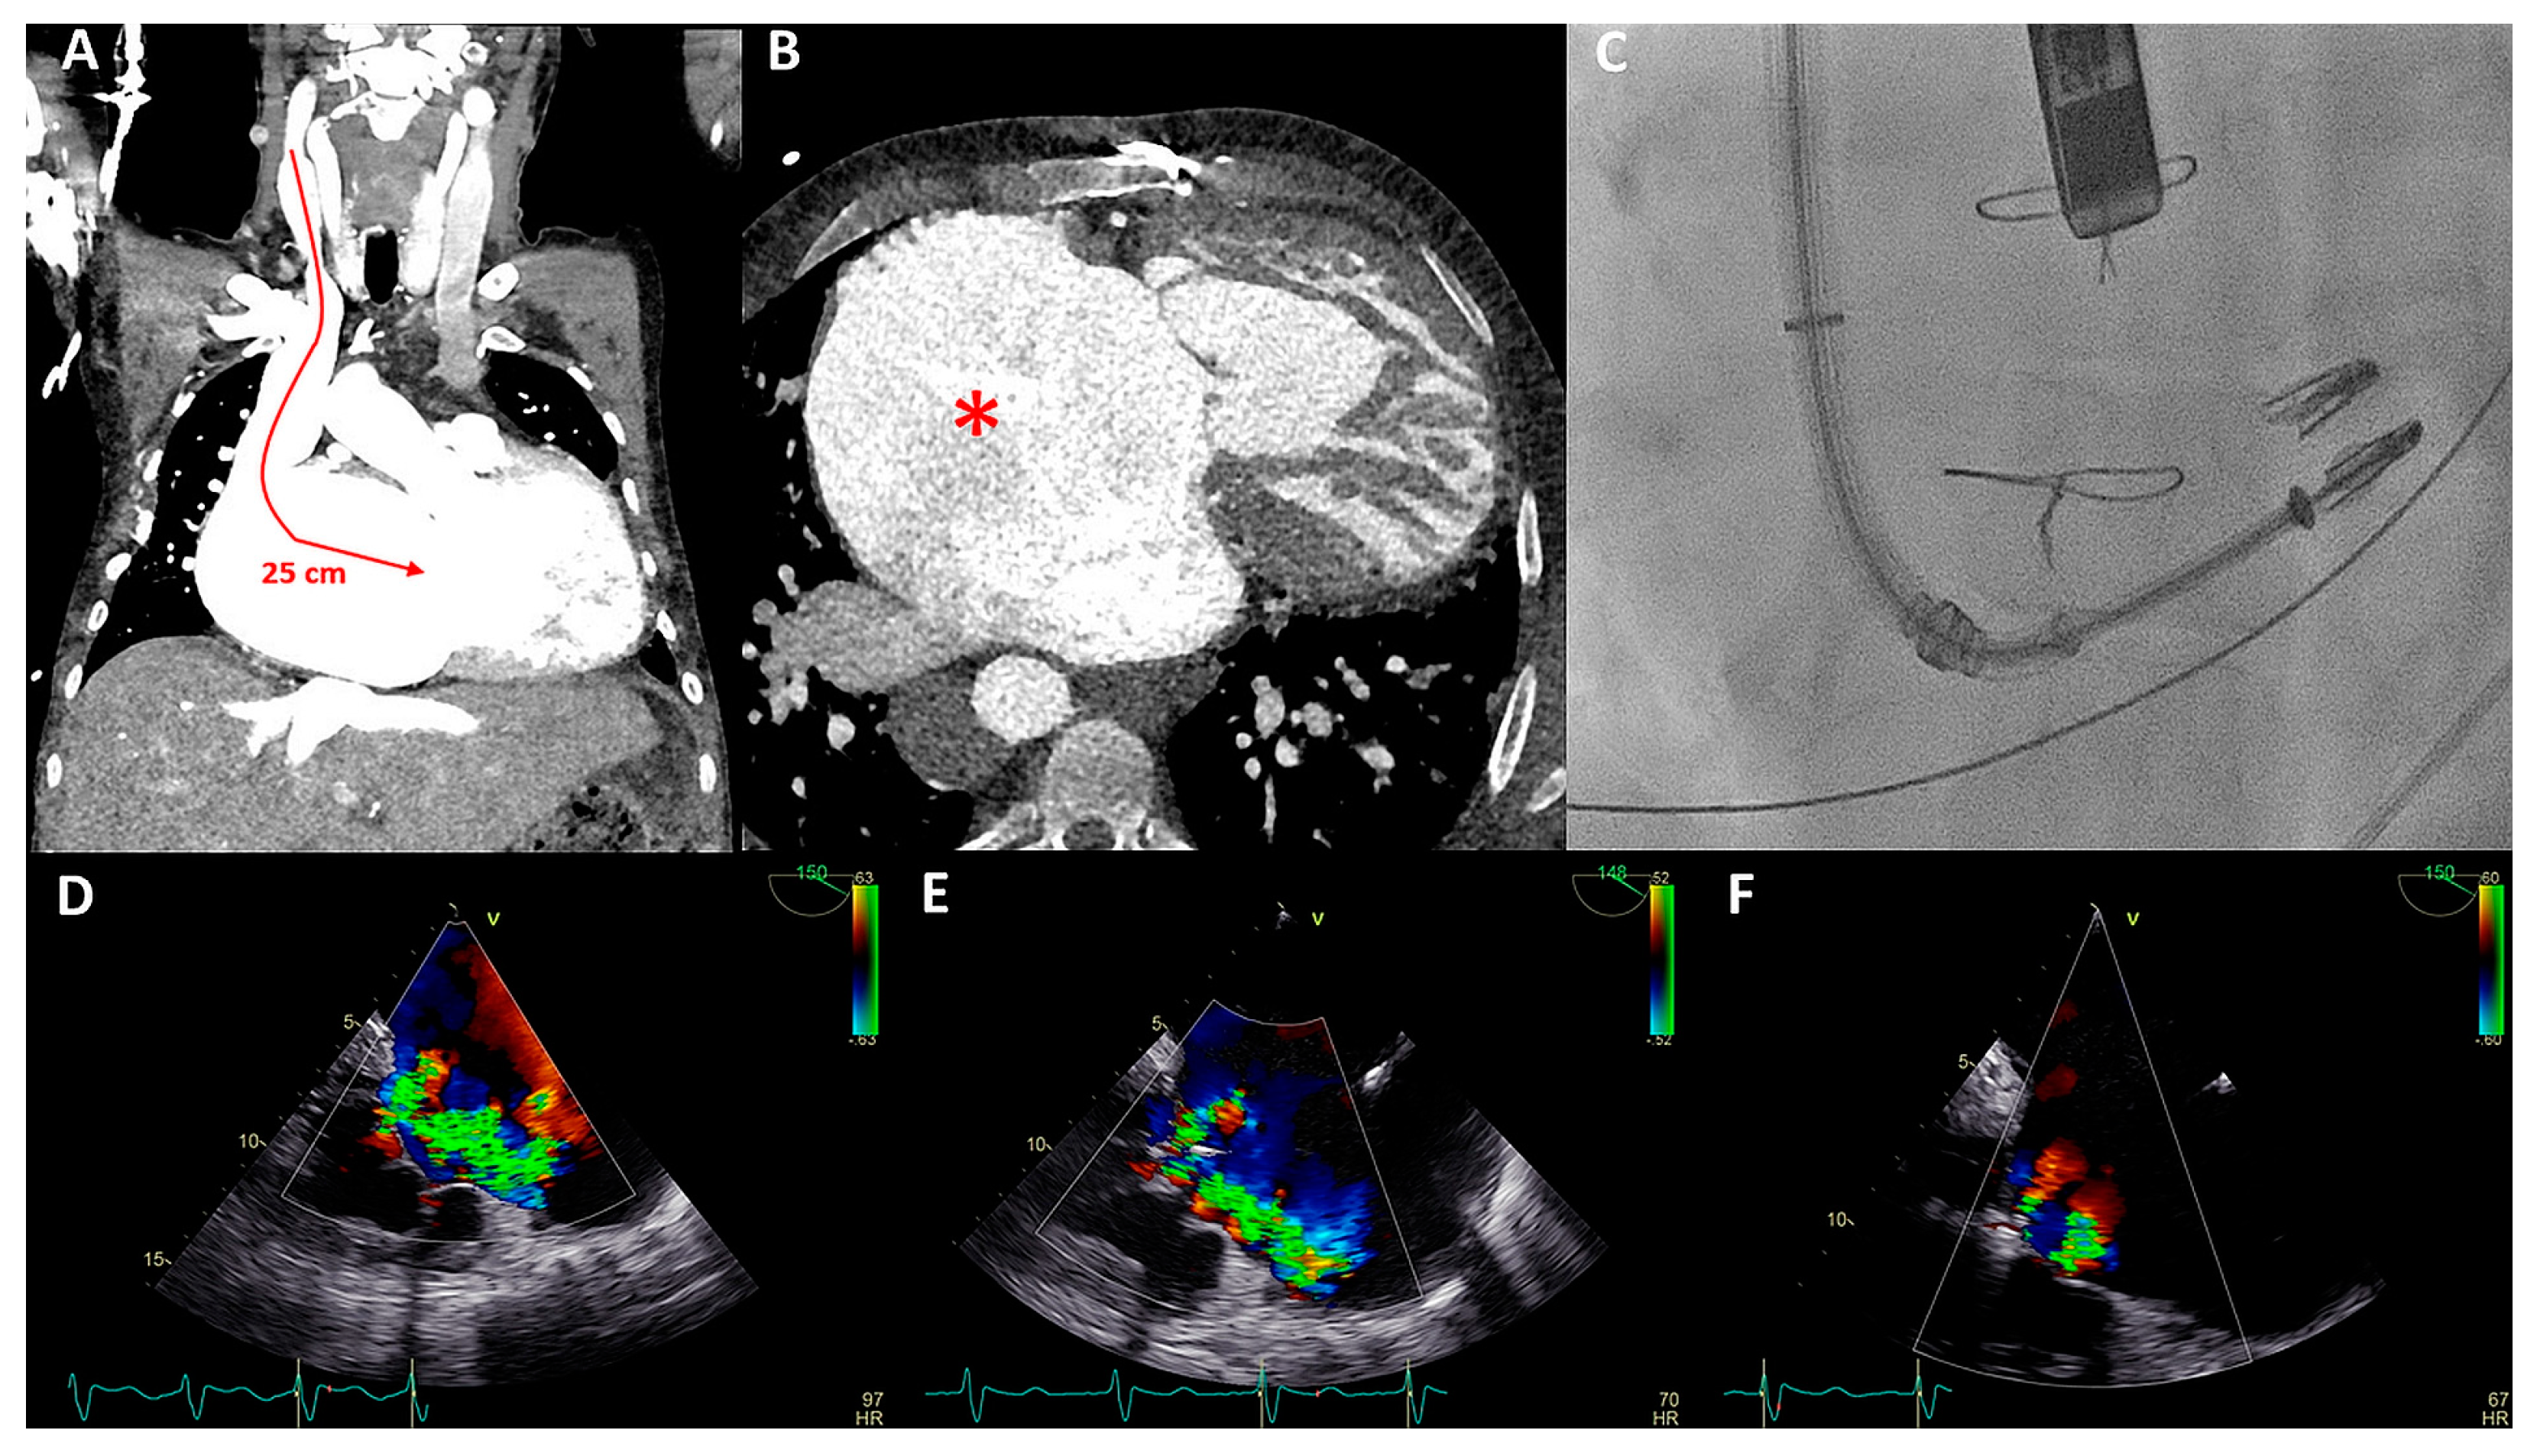

Figure 5.

(A) Distance between the right internal jugular vein and tricuspid valve (TV) measured on a computed tomography (CT) scan in a coronal plane (arrow). (B) Severely dilated mono-atrium (asterisk) on CT scan in a sagittal plane. (C) Implantation of the second XTW clip (note the first XTW clip already released) under transesophageal echocardiography (TEE) guidance. (D) Preprocedural TEE imaging of the torrential (IV+) TR. (E) Periprocedural TEE showing TR after placing the first XTW clip. (F) TEE showing the significant reduction in TR after placing the second XTW clip to grade I–II.

As a result of the severely dilated annulus and tethering, the coaptation gap was large, and simultaneous grasping of both leaflets was challenging. The TriClip system has the advanced option of independent leaflet grasping. First, the anterior leaflet (technically more challenging) was grasped and, subsequently, after minor device repositioning under TEE guidance, the septal leaflet was captured and the clip was released. The first clip was implanted near the commissure to narrow the coaptation gap so that the second clip could be implanted to treat the regurgitation (Figure 5C), which decreased to moderate (Figure 5E,F). Three weeks after the percutaneous procedure, at the outpatient clinic, the patient reported a decrease in orthopnea and exercise-induced dyspnea as the NYHA functional class was reduced from IV to III. At 17 months follow-up, the patient remained in NYHA functional class III. However, multiple heart-failure-related admissions occurred during follow-up (latest level of NT-proBNP was 8092 ng/L) and the patient developed atrial fibrillation (AF) which was treated with amiodarone.

Figure 6.

(A,B) Computed tomography (CT) scan of the thoracic cavity with the anatomical position of the dilated functional mono-atrium (asterisk) against the right thoracic wall (panel A) and bidirectional bilateral Glenn shunt (panel B) (LPA = left pulmonary artery, RPA = right pulmonary artery, LSVC = left superior vena cava, RSVC = right superior vena cava). (C) Pre-procedural transesophageal echocardiography (TEE) which visualized severe common atrioventricular (AV) valve regurgitation. (D) Anteroposterior fluoroscopic view of the two XTW MitraClips positioned in the AV valve. At the same time, it is appreciated that the delivery system is positioned through the fifth intercostal space after a right mini-lateral thoracotomy. (E) Moderate AV regurgitation after the hybrid procedure visualized with TEE.

Conventional surgical AV valve replacement or repair was considered extremely high risk due to the anatomical relation between the atrium and the thoracic wall, the extensive coronary fistulae, and the reduced ventricular function. Percutaneous AV valve replacement or repair was deemed non-feasible by the transvenous route due to interruption of the IVC with azygos continuation and sharp angulation into the mono-atrium (for a transfemoral approach). Furthermore, a transjugular approach was not feasible because of the bilateral Glenn connection. Therefore, it was decided that a hybrid procedure under general anesthesia with direct atrial access using a MitraClip delivery system (Abbott, IL, USA) was the best strategy.

The congenital cardiothoracic surgeon performed a right (mini) lateral thoracotomy in the fifth intercostal space to expose the giant mono-atrium. A double-purse string suture was placed and an incision was made to create an opening using a Safari wire for guidance and stability. The interventional cardiologist then placed two XTW clips under TEE guidance (Figure 6D), resulting in reduction in AV valve regurgitation to grade II (Figure 6E). Post-procedural TEE showed grade II regurgitation with stable position of the clips. No peri-procedural complications occurred. The patient could be discharged with adequate heart failure medication with an improvement in NYHA functional class (II). Unfortunately, the patient died after 9 months due to progressive ventricular dysfunction, worsening of the AV valve regurgitation, and heart-failure-related multi-organ dysfunction (NYHA functional class IV at the latest admission).